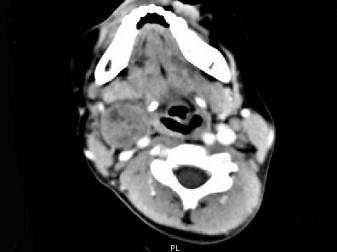

问题 女,4岁,右侧颈部可扪及一包块约两个月,无热无痛,CT如图所示,最可能的诊断为 ( )

选项 A、咽旁神经纤维瘤 B、咽旁小唾液腺混合瘤 C、咽旁副神经节瘤 D、咽旁脓肿 E、咽旁血管外皮瘤

答案 A